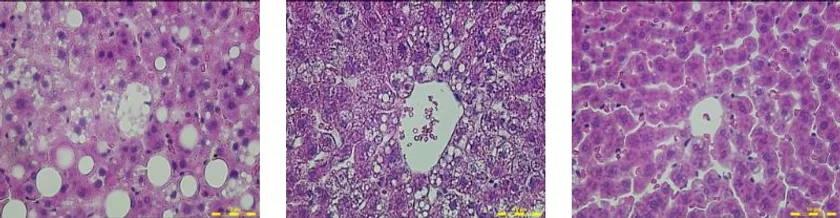

その結果、AIN-93Gを与えたラットは肥満およびNAFLDの症状を示しました。白米ではわずかに効果が見られましたが、玄米を餌に混ぜたラットはNAFLDを示しませんでした(下図参照)。また、血中の肝蔵の炎症を示す障害マーカーも、NAFLDで上昇し、玄米を食べたラットでは低下していました。

Zucker(基本飼料)群/Zucker(白米)群/Zucker(玄米)群